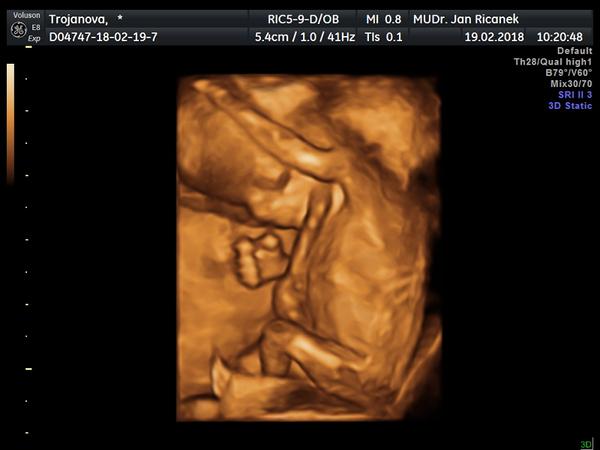

@dailik holky genetika nezklamala, je to opravdu kluk. Máme 7cm a je to pohodář a ďáblík zároveň. Dělal psí kusy při vyšetření. Děsí mě ta omotaná pupeční šňůra ale věřím mu, dle utz jsme dnes 13+1. léky vysazuji, večer už brát nemám .U vás to bude v pořádku a doporučuji vzít s sebou partnera je to nádhera-já ho bohužel s sebou neměla , protože má angínu ale všechny fotečky mám na dvd tak jsem mu je hned pustila